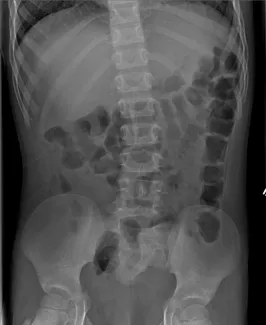

Abdominal Xrays are necessary to evaluate the effectiveness of the laxative or enema therapy and to identify the amount of stool in the colon. These will be done at each office visit.